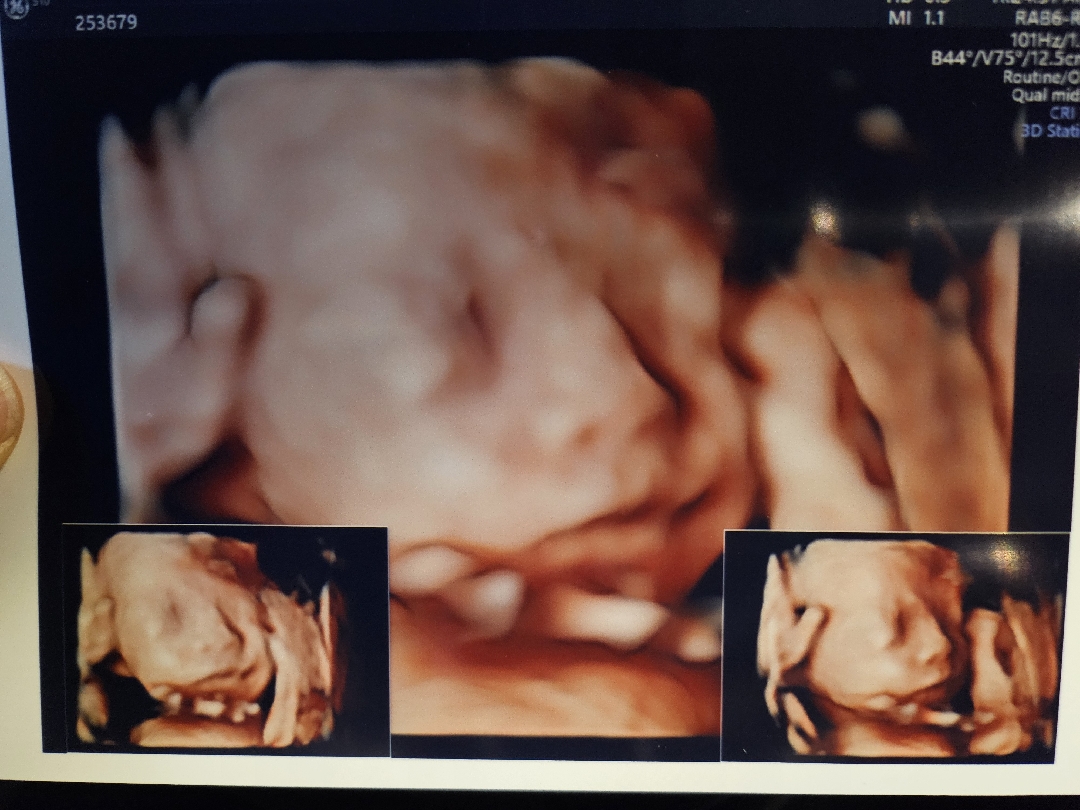

25주 촘파입니당:)

임당검사와 함께 입초봤어요~ 초음파 선생님이 아가가 폴더처럼 접혀있다고.. 오전 10시부터 보고 운동하고 돌고 5번반복하다가 11시 30분쯤 드뎌봣어요!! 정말 고마우신분이셨어요ㅎㅎ 이렇게보고나니 빨리만나고싶네용

저희 아가도 폴더처럼 접혀있었어요 😭혹시 역아이신가욤?

아뇨 그런말씀은없으셧어요~ 계속 자세바꿔 돈다고 하더라구요🤣